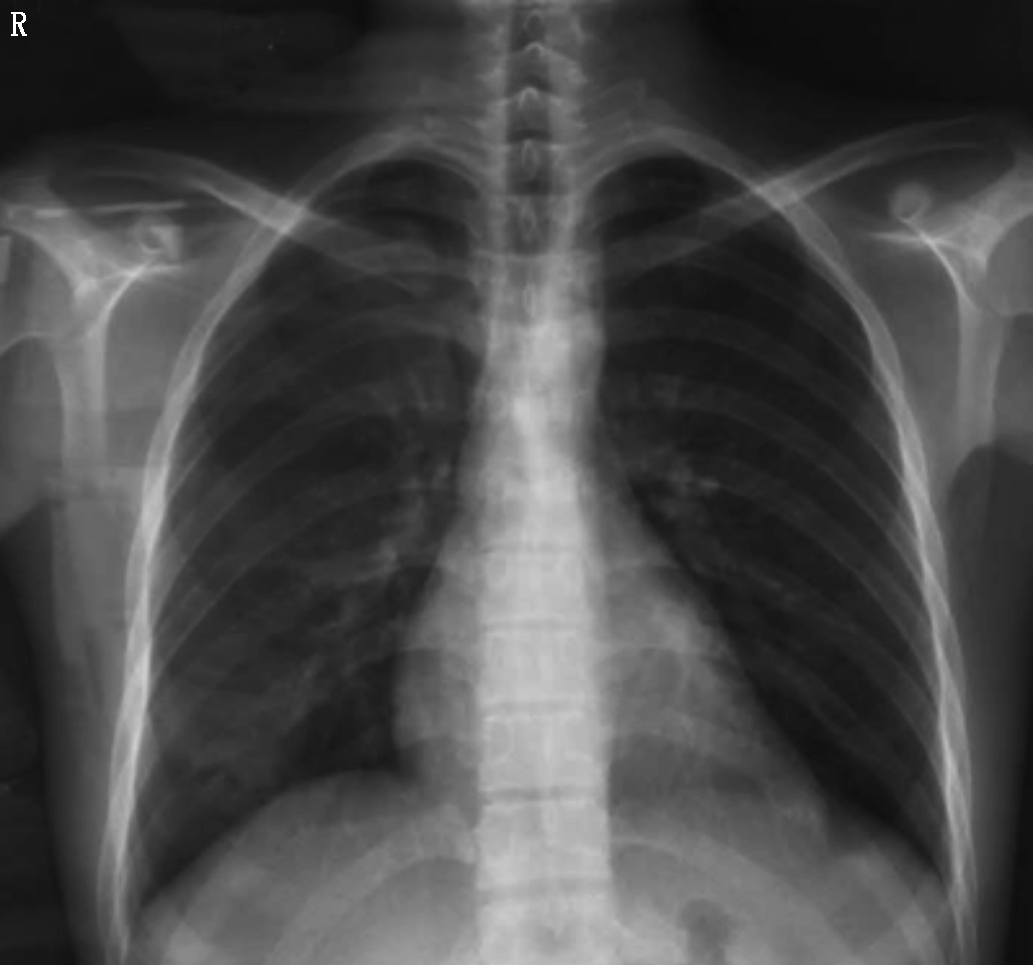

(3)胸CT检查示:双肺炎症,心包积液。

院内胸片检查显示心影明显增大,形态欠规则;两肺纹理增多、模糊,左肺中下野斑片影;左侧膈肌及肋膈角显示不清,不除外左侧胸腔积液(图2)。院内胸部CT平扫检查显示心影增大,左肺中下叶可见多处斑片影,考虑肺水肿以及慢性炎症(图3)。院内心脏MRI检查显示左心室心尖部巨大瘤样膨出;冠状动脉瘤(前降支,多发)结合临床,符合白塞氏所致心脏、冠状动脉改变;肺水肿,心包积液,双侧胸腔积液,考虑心功能不全所致(图4)。